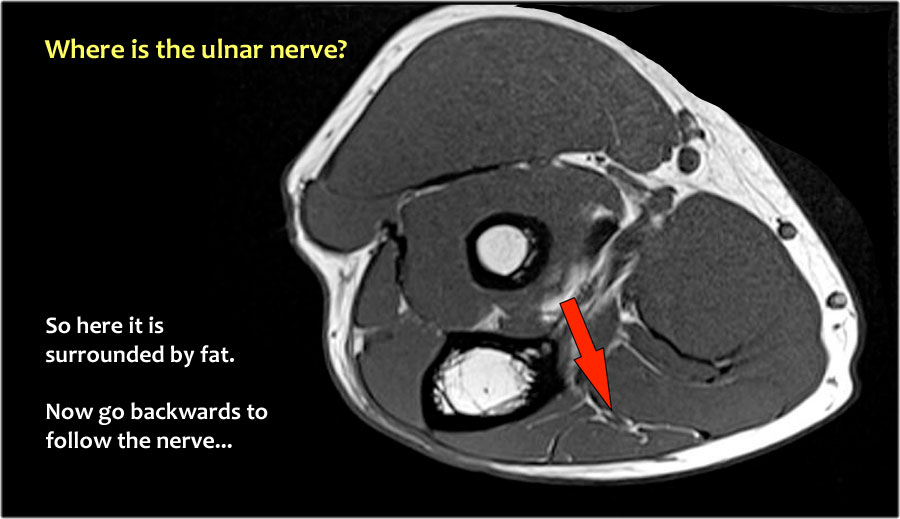

Một cách để thực hiện là đi theo các cấu trúc về phía xa cho đến khi tìm thấy dây thần kinh trụ ở phía xa tại vị trí bình thường của nó ở vùng cẳng tay gần được bao quanh bởi mô mỡ.

Sau đó khi bạn theo dõi nó về phía gần, bạn sẽ nhận thấy rằng đây là một trường hợp chuyển vị dưới da.